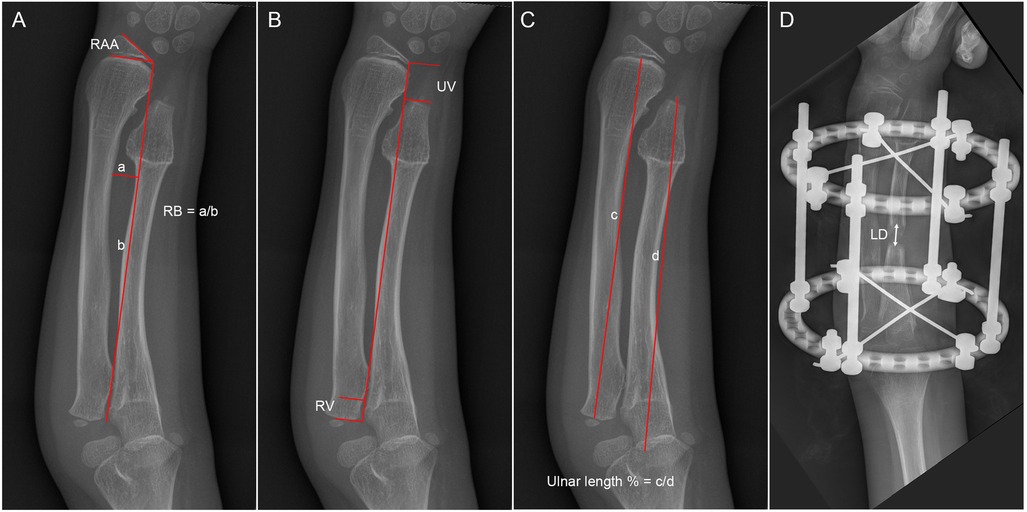

Concentric reduction of the radial head was achieved in all patients with Masada type I deformities and in 9 out of 10 patients with radial head subluxation or dislocation following the ulnar lengthening procedure (Figure 2). During long-term follow-up, one case exhibited recurrent dislocation at the humeroradial joint (Figure 3). A pin tract infection occurred in one pediatric patient but resolved following pin care and oral antibiotic administration. Non-union or neurovascular complications were not observed in any of the patients.

Figure 3

Five-panel X-ray images of a forearm. Panel A shows a normal forearm. Panel B displays the forearm with an external fixation device. Panel C shows an internal pin along the bone. Panel D depicts a healed fracture with no fixation. Panel E presents the forearm in a slightly different angle, also without fixation.

Figure 3. The preoperative and postoperative radiographical results of case 3. (A) The preoperative radiograph; (B) postoperative day 1 radiograph; (C) 1-month post-external fixator removement radiograph; (D) 3-year postoperative radiograph; and (E) 5-year postoperative radiograph.